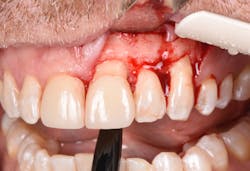

Figure 17: Patient presented with buccal vestibule swelling and complaining of pain. Swelling is visible and palpable with discoloration of the soft tissue.

Figure 18: Pre-op radiograph shows retrograde peri-implantitis possibly from previous periapical pathology.

Figure 19: Immediately after incisions and raising a full-thickness flap, suppuration was noted on the apex area of the implant.